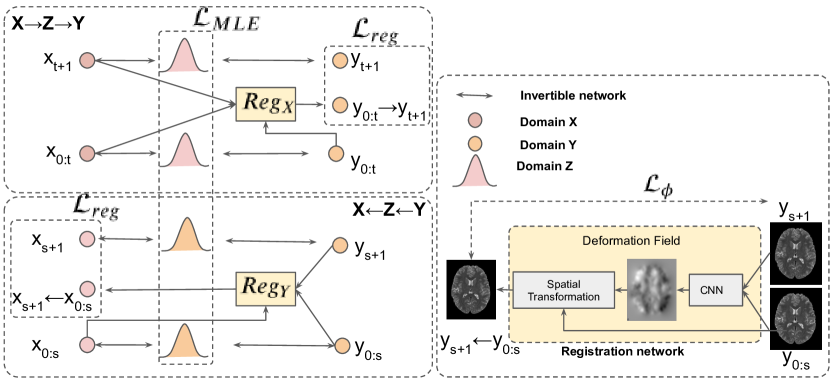

Fig. 3 illustrates the proposed network diagram for unpaired image-to-image translation. Our proposed network architecture inherits the advantages of invertible property of alignflow [5]. During training, we add two additional networks and for each domain to learn the deformation field . These additional networks only use in training time, without increasing the model complexity and inference time comparison with the baseline flow-based method. The temporal constraint via losses ensures the mapping of consecutive slices on the source domain should be consistent on the target domain. Finally, our objective function is defined as:

| (9) |

where , , , and control the relative importance of the temporal consistence losses and the two registration losses. denotes total variation (TV) loss to impose spatial smoothness by measuring the horizontal and vertical gradient of generated images [15]. These losses are weighted by .